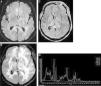

Magnetic resonance spectroscopyProton magnetic resonance spectroscopy (MRS) allows for the semiquantitative evaluation of in vivo tissue to measure metabolites, such as N-acetylaspartate (NAA), choline (Cho), creatinine (Cr), lactate (Lac), and lipids (Lip). In PCNSL, MRS has demonstrated elevated Lip and Lac peaks, high Cho/Cr ratios, decreased NAA levels and high Cho/NAA ratios (Figure 1).4,11,16,17 The presence of Lac or Lip at baseline has been associated with poor progression-free and overall survival.11

Diffuse large B-cell lymphoma in the corpus callosum. An axial T1 image after intravenous gadolinium administration (A) shows a homogeneous enhanced mass in the splenium of the corpus callosum, which is predominantly in the right hemisphere (arrow). An axial apparent diffusion coefficient map (B) confirmed a very low signal intensity in the solid lesion. Note the hyperintensity of the perilesional vasogenic edema. Proton magnetic resonance spectroscopy (C) shows decreased N-acetylaspartate levels and high choline/N-acetylaspartate and choline/creatinine ratios. Note the increased lipid and lactate peaks (0.9–1.3ppm). A magnetic resonance perfusion sequence (dynamic susceptibility contrast magnetic resonance image T2*) (D) confirmed the absence of neoangiogenesis (low relative cerebral blood volume). Note the high percentage of signal intensity recovery (the ascending part of the curve above the baseline as indicated by the vertical arrowheads).

PCNSL grow rapidly and behave similar to high-grade brain tumors with evidence of high cell membrane turnover on MRS (a high Cho peak), neuronal damage (decreased NAA levels), and anaerobiosis (high lactate levels).4,11,16,17 These findings are similar to those for high-grade gliomas and metastases; however, the presence of this MRS pattern may help in the differential diagnosis of brain toxoplasmosis in immunocompromised patients, which typically exhibits elevated Lip peaks and no significant increases in Cho or its ratios.1,4,11